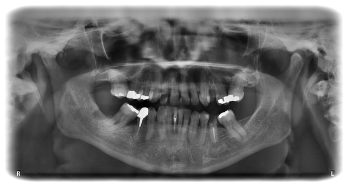

Zahnfarbene Kunststofffüllungen

Compositefüllungen stellen heutzutage den Stand der Technik in der Füllungstherapie dar. Composite ist eine Mischung aus Keramikpartikeln und einer Kunststoff-matrix, mit der Zähne langzeitstabil, metallfrei und ästhetisch versorgt werden können.